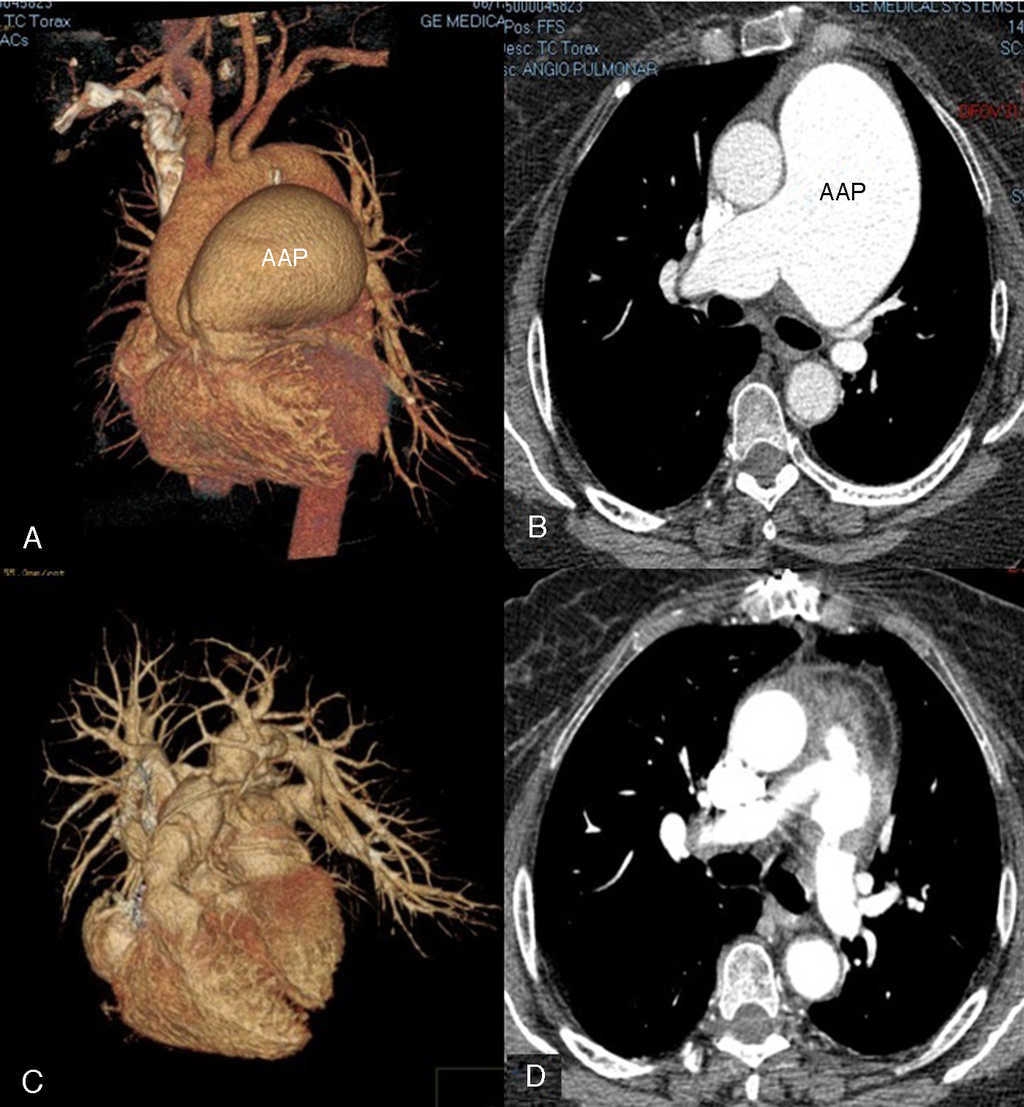

Presentamos el caso clínico de una paciente femenina de 61 años de edad con antecedentes de hipertensión arterial sistémica de 10 años de evolución, quien acudió a nuestro hospital por presentar disnea, tos y dolor precordial de un año de evolución; la exploración del tórax evidenció disminución del murmullo vesicular y estertores subcrepitantes diseminados. En el área cardiaca se encontró el segundo ruido pulmonar incrementado en intensidad, desdoblado, fijo, y con presencia de soplo holosistólico tricuspídeo. Se le documentó por ecocardiografía dilatación del tronco de la AP de 66 mm de diámetro, con diámetros de 23 mm en la rama derecha y 34 mm en la rama izquierda, además de insuficiencia pulmonar severa, la presión sistólica de la AP de 47 mmHg y la excursión sistólica del plano del anillo tricuspídeo (TAPSE, por sus siglas en inglés) de 23 mm, el diámetro diastólico del ventrículo derecho (VD) de 30 mm, la válvula tricúspide reportada con insuficiencia ligera. En la gammagrafía pulmonar se observó hipoperfusión generalizada en ambos pulmones y en la angiotomografía pulmonar (fig. 1, A y B) se corroboró la dilatación aneurismática del tronco de la AP y compresión de ambas ramas secundarias, sin evidencia de trombos, lo que explicó los defectos en la perfusión antes documentados.

Figura 1 Angiotomografía del aneurisma de la arteria pulmonar principal. 1A: imagen tridimensional prequirúrgica del aneurisma de la arteria pulmonar por angiotomografía pulmonar. 1B: imagen axial prequirúrgica del aneurisma de la arteria pulmonar. 1C: imagen tridimensional de la reconstrucción posquirúrgica del aneurisma de la arteria pulmonar. 1D: imagen axial posquirúrgica de la reconstrucción del aneurisma de la arteria pulmonar. AAP: aneurisma de la arteria pulmonar.

En el seguimiento a 90 días se documentó regresión por ecocardiografía de las cavidades derechas (grosor de la pared del VD 7 mm, diámetro diastólico del VD 27 mm), con adecuada movilidad y sin gradiente transvalvular significativo en la región del xenoinjerto. La TAC mostró una zona de estrechamiento a mitad de la neoarteria que correspondió a la válvula del xenoinjerto, además disminución del diámetro del tronco de la AP a 37 mm (fig. 1, C y D).